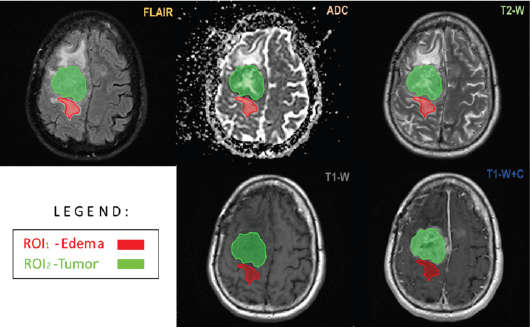

Figure 1: Volumetric brain multiparametric MR imaging used for parametric response map construction after chemoradiation in a 55-year-old male patient with a right temporal GBM. The axial FLAIR image demonstrates segmentation (red and green) of the region of FLAIR hyper-intensity corresponding to the area of edema/ tumor infiltration. Notice the segmented enhancement that has been confirmed and segmented on the ADC map, T1W, T1WI post-contrast, and T2W.

The brain was one of the first sites to be imaged by MRI for RTP. MRI provides better tumor and normal tissue delineation than CT; therefore, it is more frequently used in treatment planning systems for tumor contouring in high dose focal brain radiotherapy such as fractionated radiotherapy (RT), Fractionated stereotactic radiotherapy (FSRT), and stereotactic radiosurgery (SRS) (Figure 1 & 2). We scan patients with MRI using a standard 16 or 32 channel RF head coil with a thermoplastic immobilizer or stereotactic radiosurgery frame in treatment position, and perform the register of the MRI image set to the CT simulation image set in the treatment planning process. MRI can be used for guided radiotherapy during diagnostic and post-treatment response measurements.

Clinically, high-grade brain tumor boundaries such as those in glioblastoma (GBM) can be highlighted on contrast-enhanced T1-weighted images such as those acquired with T1-weighted magnetization-prepared radio-frequency pulses and rapid gradient-echo (MPRAGE) as well as regular T2-weighted images [23]. Fast fluid-attenuated inversion recovery (FLAIR) images have also been found useful to define tumor edema and possible infiltration [24]. For high grade brain tumors such as GBM T1- weighed high resolution isotropic 3D images acquired postcontrast are being used for tumor contouring and determination of gross target volume (GTV), while a series of T2-weighed and FLAIR images define the clinical target volume (CTV). For brain metastasis and low grade or benign brain tumors there is no tumor invasion to normal brain tissue; therefore, post-contrast high resolution 3D T1-weighted images are sufficient for tumor delineation, especially for SRS treatments (Figure 3).